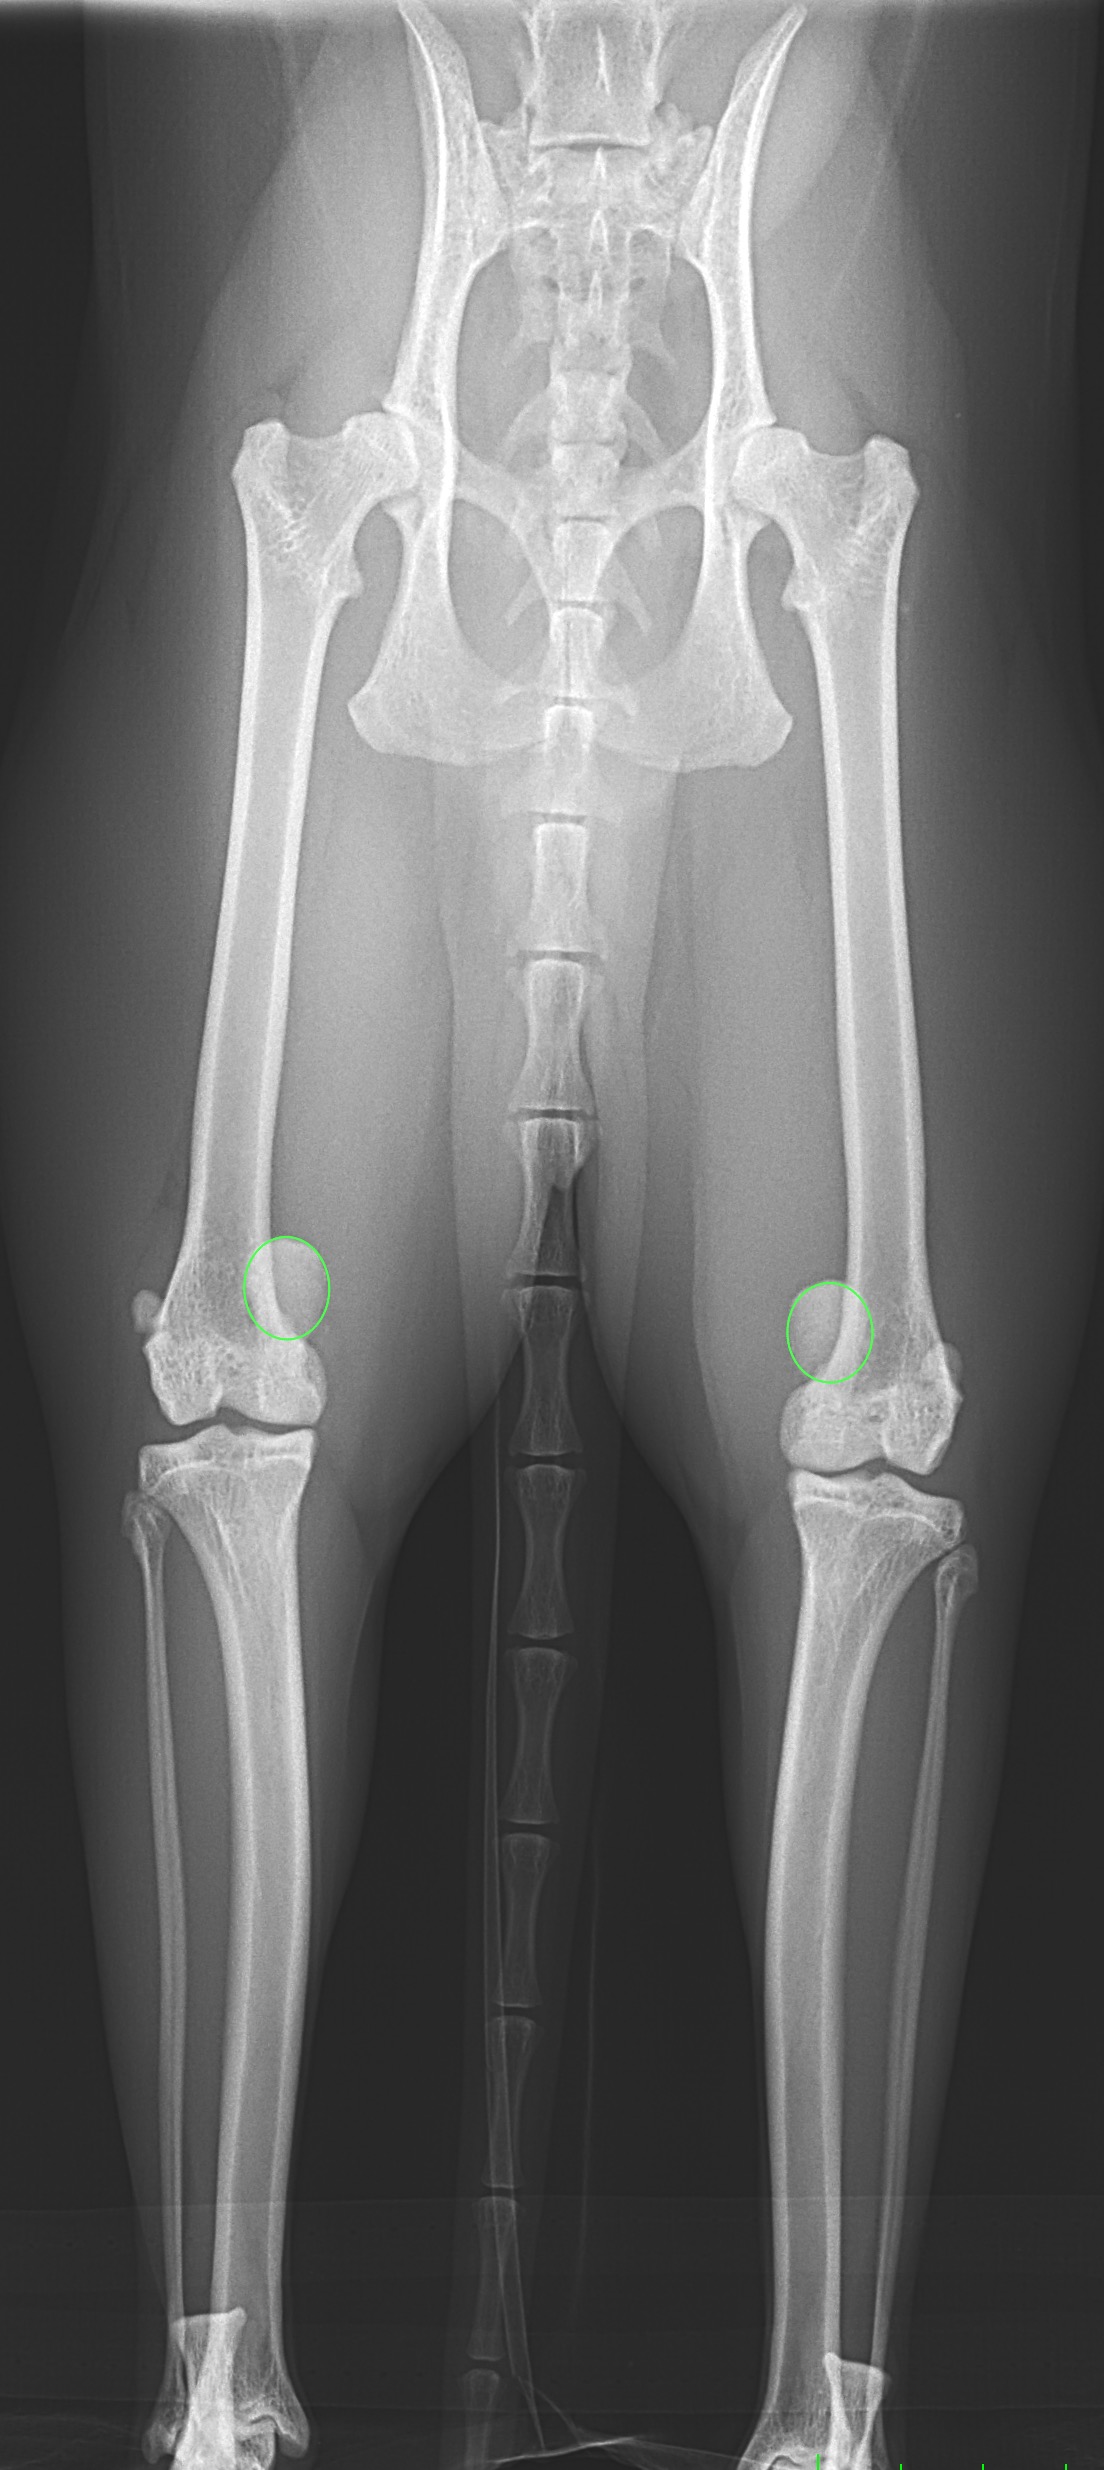

猫も犬と同様に膝蓋骨の問題は起こります。習慣性の膝蓋骨脱臼による異常なメカニカルによる負荷が関節軟骨に生じています。外科的に大腿骨滑車深化術、脛骨粗面移行術によるアライメント手術を行います。また、内科療法としてPRP:自己多血小板血漿を関節内に投与、レーザー照射、カルトロフェン・ベット、NSAIDs、アンチノールなどのサプリメントを継続します。